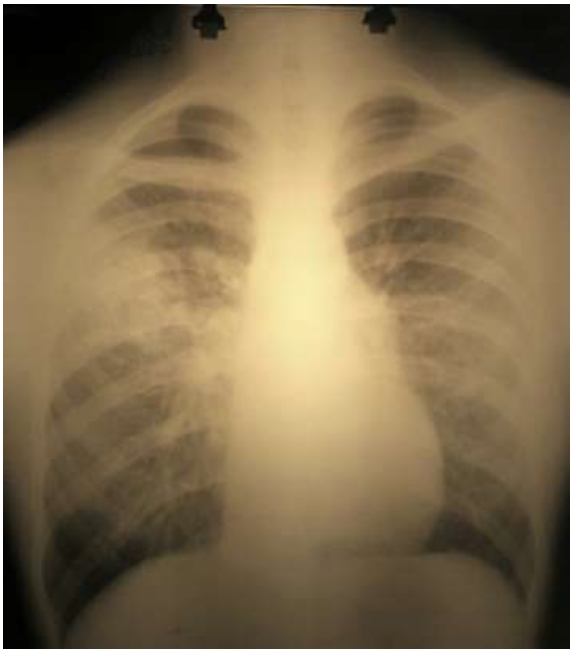

При рентгенологическом обследовании органов грудной клетки выявлялись в легких очаги негомогенной инфильтрации, более плотные у корня, с неровными краями, часто тяжистые, «мохнатые», двусторонние, несимметричные, чаще наблюдаются в нижних отделах легких. Реакция со стороны плевры наблюдалась у 16 пациентов (15,1%) и ограничивалась междолевой плеврой.

Преимущественно отмечалось правостороннее поражение легких (48,8%) в виде полисегментарного поражения, в 34,1 % случаев – левосторонняя пневмония, у 14 пациентов – двусторонняя (17,1%) (рис. 5). Деструктивное поражение верхней доли правого легкого отмечалось у пациента с тяжелым органическим поражением ЦНС на фоне анемии средней степени тяжести вследствие сочетанной бактериальногрибковой инфекции (M. Pneumoniae+ S. aureus + С. аlbicans + K. Pneumoniae).

Рис. 5. Рентгенограмма органов грудной клетки ребенка В., 13 лет